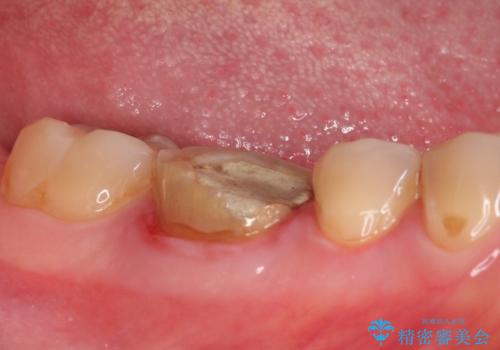

根管内を見てみると、近心根は本来の根管とは違うところを削られて髄床底でパーフォレーションを起こしていました。

パーフォレーション部位に関しては、口腔内との交通がなければMTAセメントを用いて修復することで、高い予知性を期待できます。